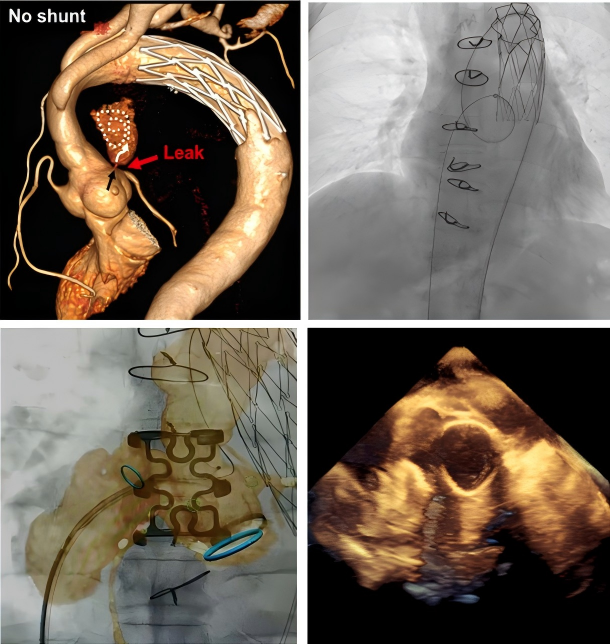

图说:

患者,男,61岁,升主动脉替换+全弓支架象鼻术后,窦管交界处吻合口漏

图A,B:主动脉CT三维重建从不同角度展示吻合口漏;

图C,D:主动脉CT和DSA显示吻合口漏与左冠状动脉关系和距离;

图E:术中封堵器释放前,复查造影,显示LCA开口显影良好;

图F:释放封堵器后复查造影,证实冠状动脉显影良好,不受封堵器伞盘影响;

图G:术后1个月复查主动脉CTA,提示封堵器位置良好,LCA显影良好;

图H:吻合口漏完全封闭,假性动脉瘤完全血栓化。